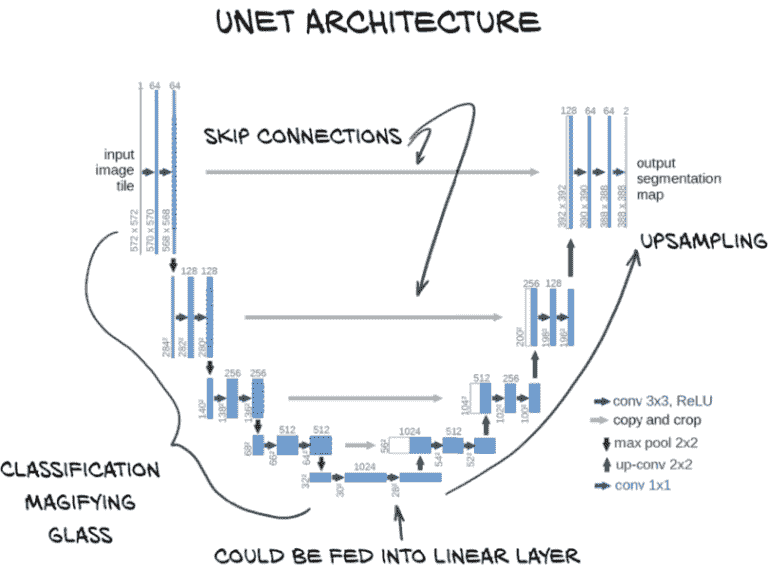

13.3.1 U-Net 架构

在我们陷入可能的上采样算法的兔子洞之前,让我们回到本章的目标。根据图 13.6,第一步是熟悉一个名为 U-Net 的基础分割算法。

图 13.6 我们将使用的分割新模型架构

U-Net 架构是一种可以产生像素级输出的神经网络设计,专为分割而发明。从图 13.6 的突出部分可以看出,U-Net 架构的图表看起来有点像字母U,这解释了名称的起源。我们还立即看到,它比我们熟悉的大多数顺序结构的分类器要复杂得多。不久我们将在图 13.7 中看到 U-Net 架构的更详细版本,并了解每个组件的具体作用。一旦我们了解了模型架构,我们就可以开始训练一个来解决我们的分割任务。

图 13.7 来自 U-Net 论文的架构,带有注释。来源:本图的基础由 Olaf Ronneberger 等人提供,来源于论文“U-Net:用于生物医学图像分割的卷积网络”,可在arxiv.org/abs/1505.04597和lmb.informatik.uni-freiburg.de/people/ronneber/u-net找到。

图 13.7 中显示的 U-Net 架构是图像分割的一个早期突破。让我们看一看,然后逐步了解架构。

在这个图表中,方框代表中间结果,箭头代表它们之间的操作。架构的 U 形状来自网络操作的多个分辨率。顶部一行是完整分辨率(对我们来说是 512×512),下面一行是其一半,依此类推。数据从左上流向底部中心,通过一系列卷积和下采样,正如我们在分类器中看到的并在第八章中详细讨论的那样。然后我们再次上升,使用上采样卷积回到完整分辨率。与原始 U-Net 不同,我们将填充物,以便不会在边缘丢失像素,因此我们左右两侧的分辨率相同。

早期的网络设计已经具有这种 U 形状,人们试图利用它来解决完全卷积网络的有限感受野大小问题。为了解决这个有限的感受野大小问题,他们使用了一种设计,复制、反转并附加图像分类网络的聚焦部分,以创建一个从精细详细到宽感受野再到精细详细的对称模型。

然而,早期的网络设计存在收敛问题,这很可能是由于在下采样过程中丢失了空间信息。一旦信息到达大量非常缩小的图像,对象边界的确切位置变得更难编码,因此更难重建。为了解决这个问题,U-Net 的作者在图中心添加了我们看到的跳跃连接。我们在第八章首次接触到跳跃连接,尽管它们在这里的应用方式与 ResNet 架构中的不同。在 U-Net 中,跳跃连接将输入沿着下采样路径短路到上采样路径中的相应层。这些层接收来自 U 较低位置的宽感受野层的上采样结果以及通过“复制和裁剪”桥接连接的早期精细详细层的输出作为输入。这是 U-Net 的关键创新(有趣的是,这比 ResNet 更早)。

所有这些意味着这些最终的细节层在最佳状态下运作。它们既具有关于周围环境的更大背景信息,又具有来自第一组全分辨率层的精细详细数据。

最右侧的“conv 1x1”层位于网络头部,将通道数从 64 改变为 2(原始论文有 2 个输出通道;我们的情况下有 1 个)。这在某种程度上类似于我们在分类网络中使用的全连接层,但是逐像素、逐通道:这是一种将最后一次上采样步骤中使用的滤波器数量转换为所需的输出类别数量的方法。